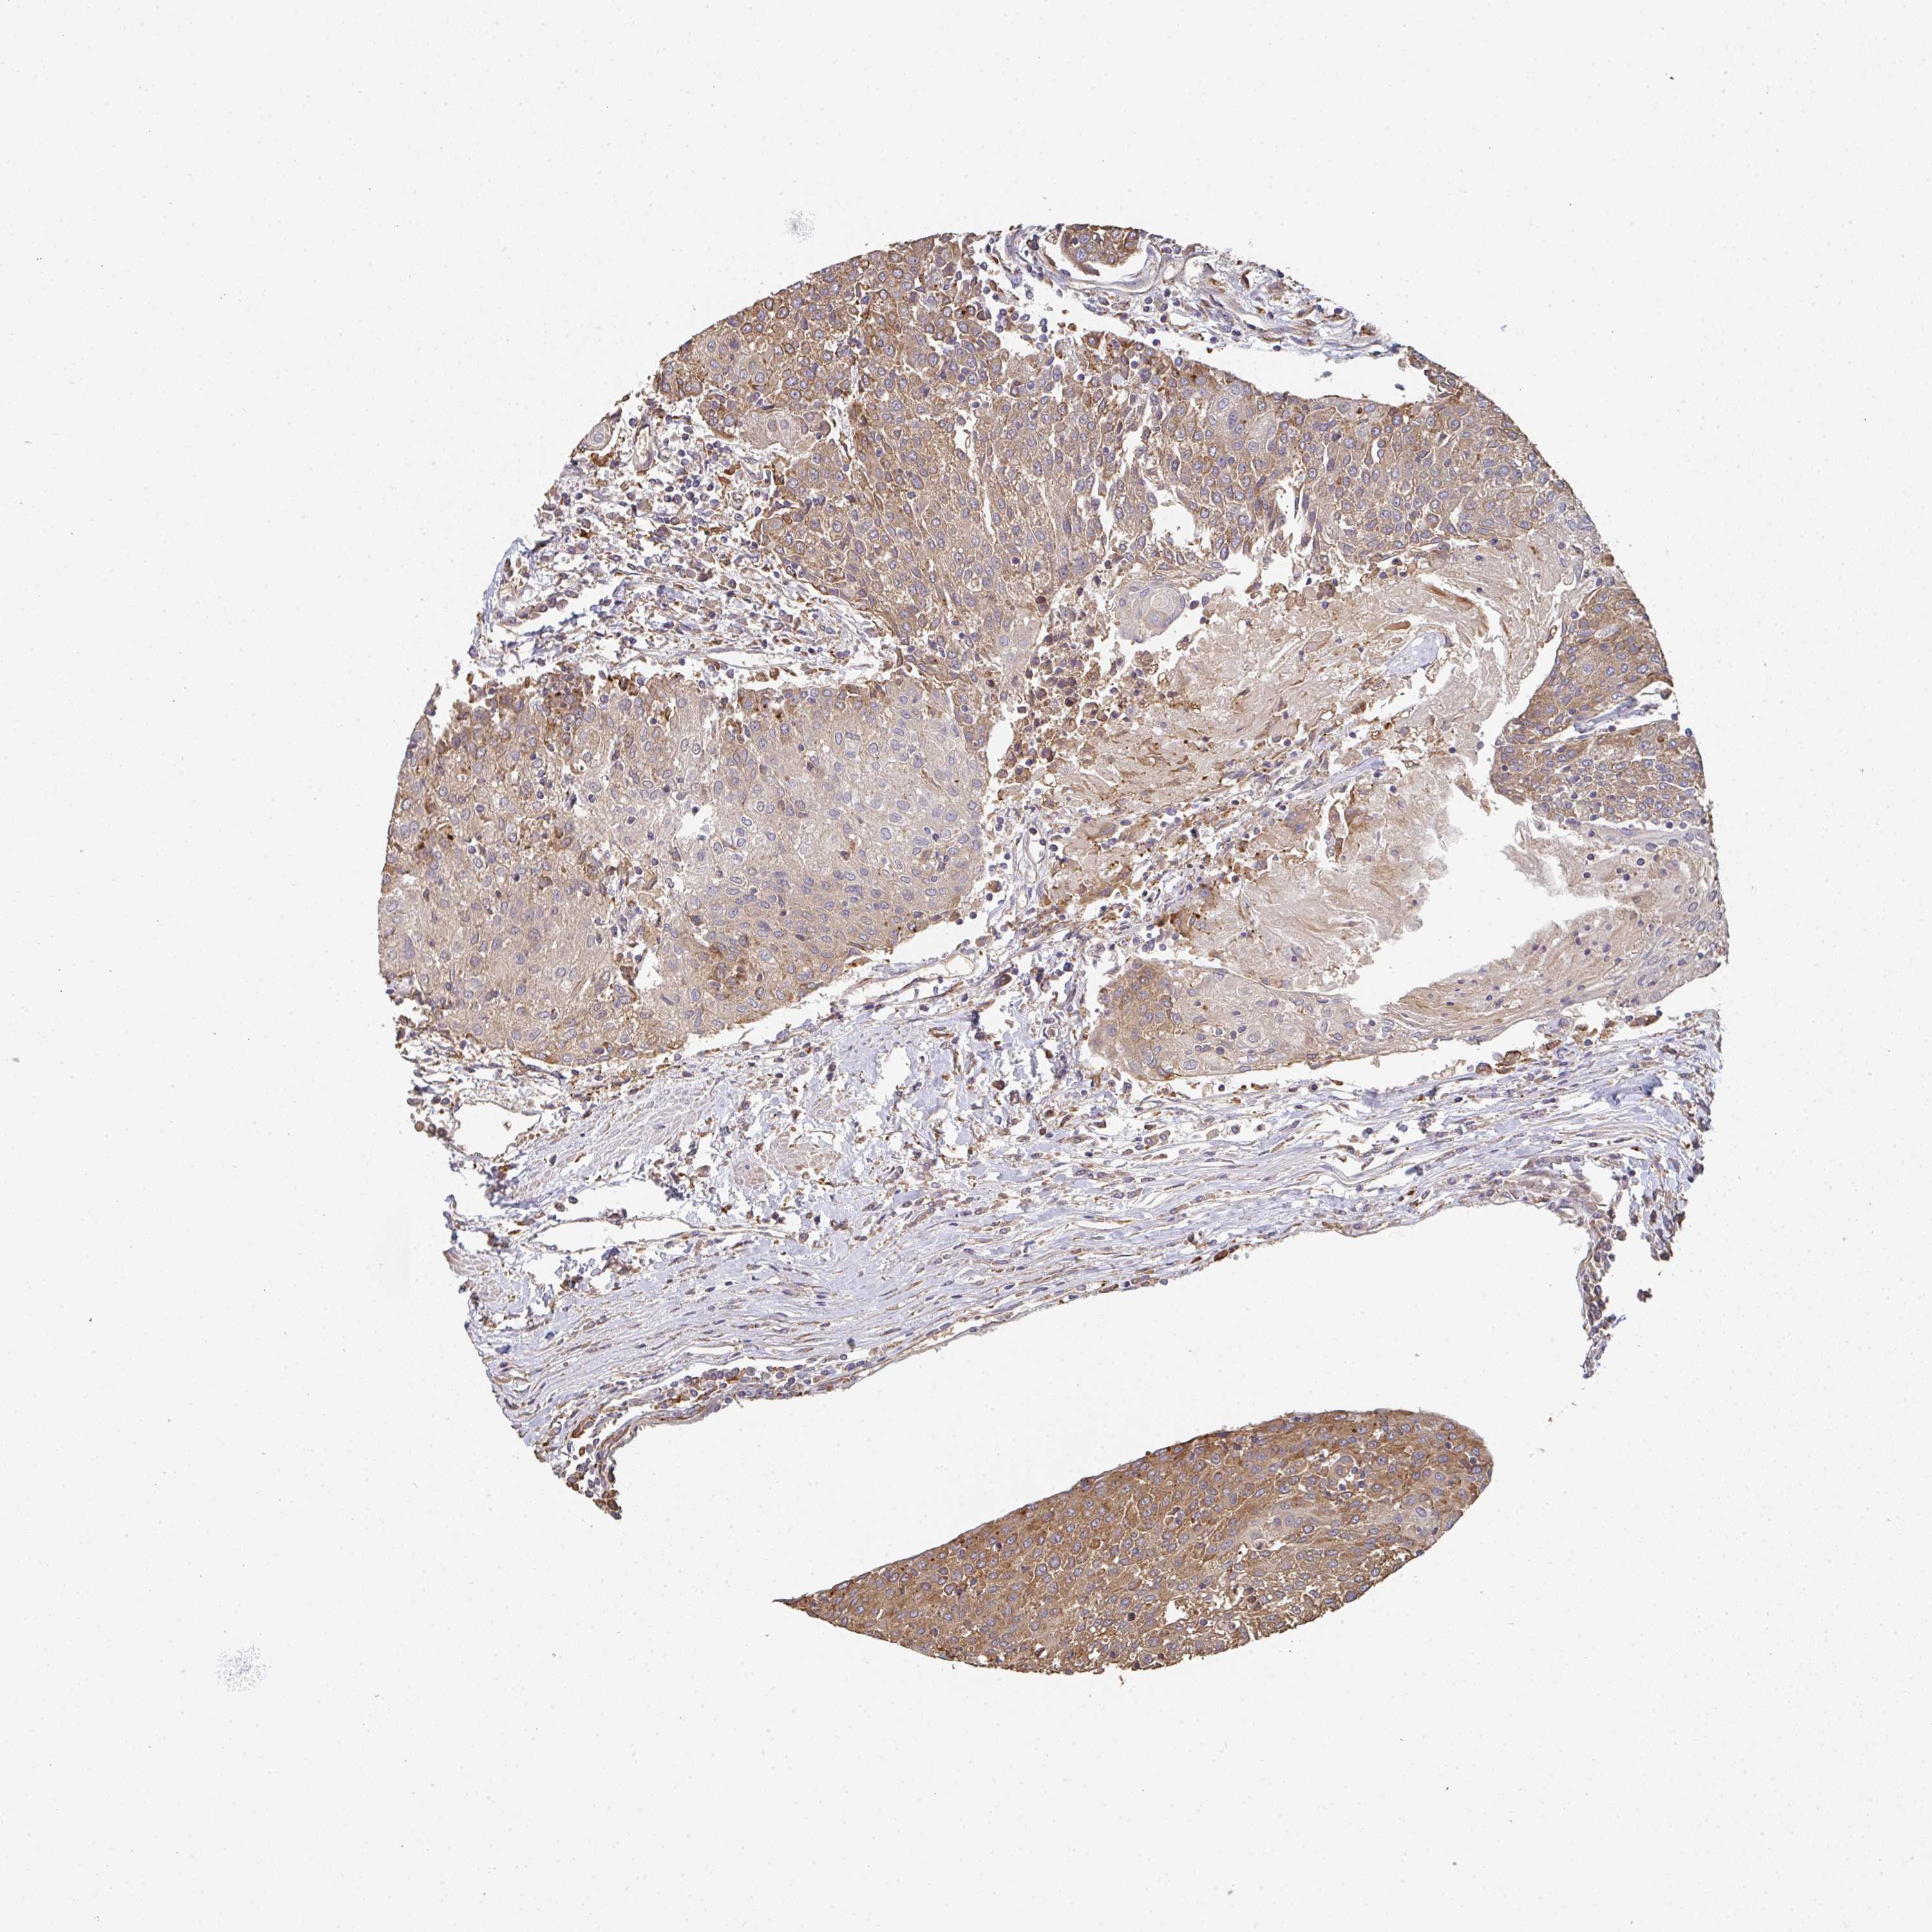

UROTHELIAL CANCER - Protein expressioni

A mouse-over function shows sample information and annotation data. Click on an image to view it in a full screen mode. Samples can be filtered based on level of antibody staining by selecting one or several of the following categories: high, medium, low and not detected. The assay and annotation is described here.

Antibody stainingi

Antibody staining in the annotated cell types in the current human tissue is reported as not detected, low, medium, or high, based on conventional immunohistochemistry profiling in selected tissues. This score is based on the combination of the staining intensity and fraction of stained cells.

Each image is clickable and will lead to virtual microscopy that enables deeper exploration of all samples and also displays staining intensity scores, fraction scores and subcellular localization as well as patient and tissue information for each sample.

Antibody HPA056821

Staining

High

Medium

Low

Not detected

Intensity

Strong

Moderate

Weak

Negative

Quantity

>75%

75%-25%

<25%

None

Location

Nuclear

Cytoplasmic/membranous

Cytoplasmic/membranous,nuclear

Urothelial carcinoma, High grade

Urothelial carcinoma, Low grade